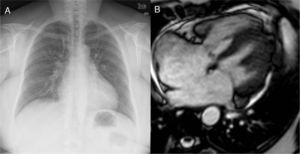

Fifty-two-year old patient with a late diagnosis of ostium secundum-type of IAC. (A) Cardiomegaly chest X-ray and larger caliber of pulmonary arteries suggestive of pulmonary hypertension. This finding should trigger all the alarms when it comes to the need for calculating the Qp/Qs before surgery. (B) Steady state image in a 4-chamber view/plane in ventricular systole showing a large IAC. The measurement of the Qp/Qs was 1.3–very low given the importance of the anatomic defect. Even though it is compatible with pulmonary hypertension this is not suggestive of shunt inversion (Eissenmenger syndrome).